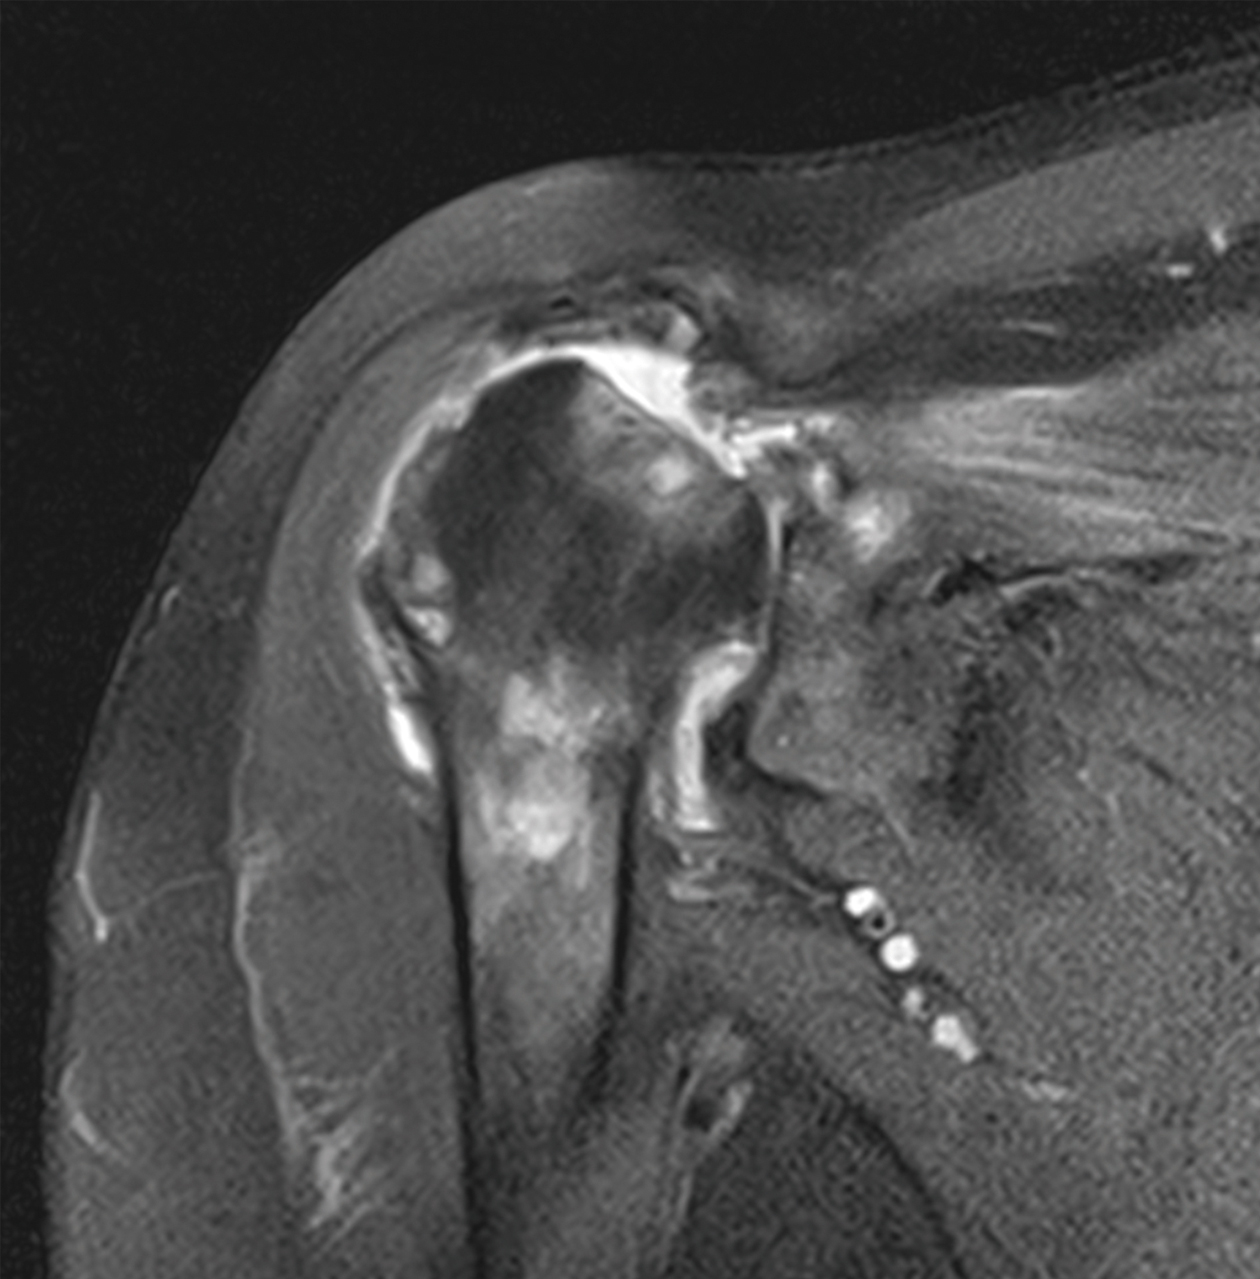

黃先生52歲,左肩疼痛多年,手無法上舉,一年來症狀加劇,經檢查發現肱骨頭缺血性壞死併肩關節炎,核磁共振發現大片全層旋轉肌破裂,接受了反置式人工全肩關節置換手術治療,並投入計劃性復健治療,目前疼痛消失,手已可上舉接近150度。

左側肱骨頭缺血性壞死續發關節炎併旋轉肌腱斷裂,經反置式人工全肩關節置換手術治療。